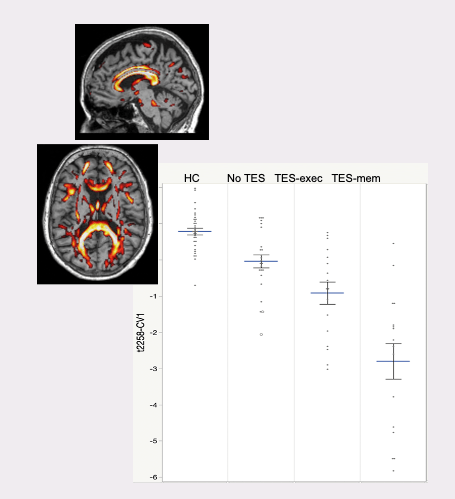

Persons who experience repeated impact to the head, such as in contact sports, military combat, or multiple falls, can be at risk for the development of long term effects. In some cases this can result in Chronic Traumatic Encephalopathy (CTE), a devastating neurodegenerative disease. Yet today there is no diagnostic test to determine how impact is affecting the brain. ADMdx is developing diagnostic tools using brain imaging to detect these effects and identify whether someone is likely to have CTE.

In collaboration with the Cleveland Clinic Lou Ruvo Center for Brain Health, ADMdx has demonstrated the ability to differentiate the effects of repetitive head impact from those due to Alzheimer’s disease. We are continuing this work through a $2 million grant funded by the National Institutes of Health, with collaborators from the Cleveland Clinic, Boston University, and Indiana University.